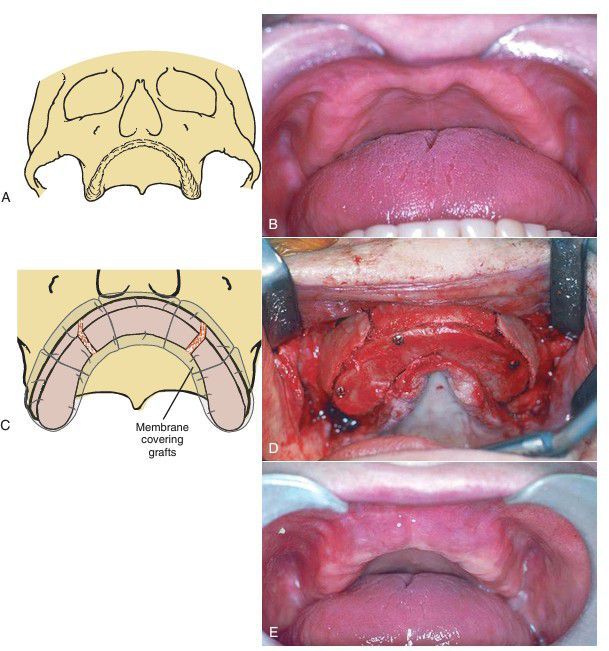

(A) Diagram of atrophic maxilla. (B) Clinical photograph illustrating inadequate alveolar ridge for reconstruction. (C) Three segments of bone are secured in place. (D) Stabilization of the onlay grafting with rigid fixation. Small defects are filled with cancellous bone and bone morphogenetic protein. A resorbable membrane is then placed over the graft prior to tissue closure. (E) Postoperative result demonstrating improved alveolar ridge height and contour.